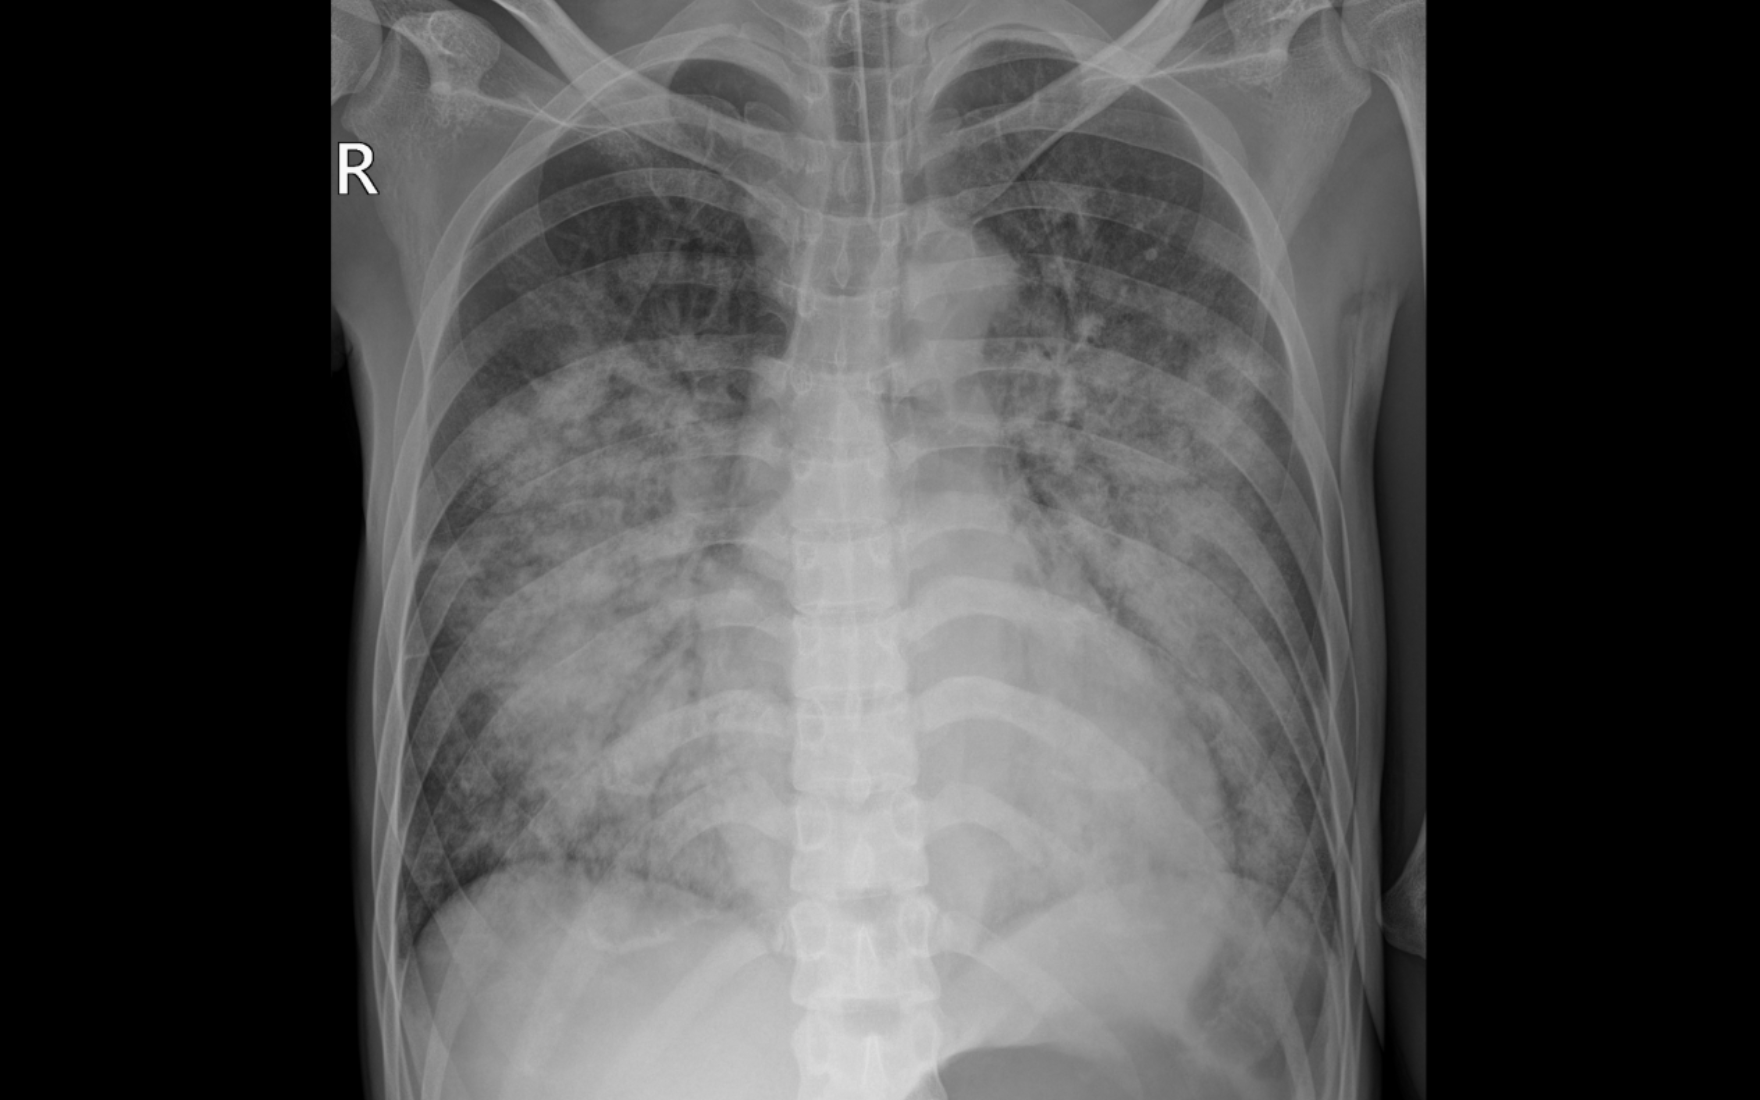

Phim chụp X quang thể hiện tổn thương mờ, lan tỏa 2 phổi của bệnh nhân